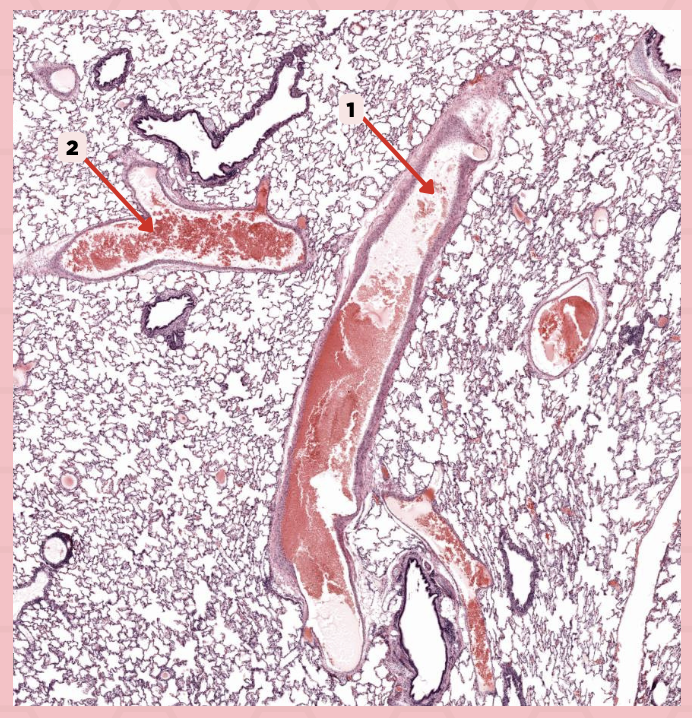

Deoxygenated blood

What type of blood does vessel No. 1 carry?

Connective tissue septae

Where would No. 2 be located?

Pulmonary artery

Identify the structure labeled as 1.

Tributary of pulmonary vein

Identify the structure labeled as 2.

Oxygenated blood

What type of blood does this vessel supply?

Bronchial artery

Identify the structure labeled as 1.